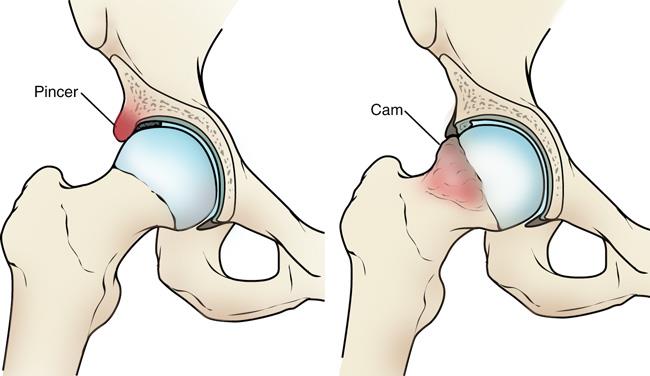

Femoroacetabular Impingement (FAI):

- FAI is a condition where there is abnormal contact between the femoral head (ball) and the acetabulum (socket), leading to joint damage and pain. There are two types of FAI:

- Cam Impingement: A deformity of the femoral head.

- Pincer Impingement: A condition where the acetabulum covers too much of the femoral head.

- Arthroscopic Treatment: Surgeons can trim or reshape the bone to reduce impingement and improve joint movement.